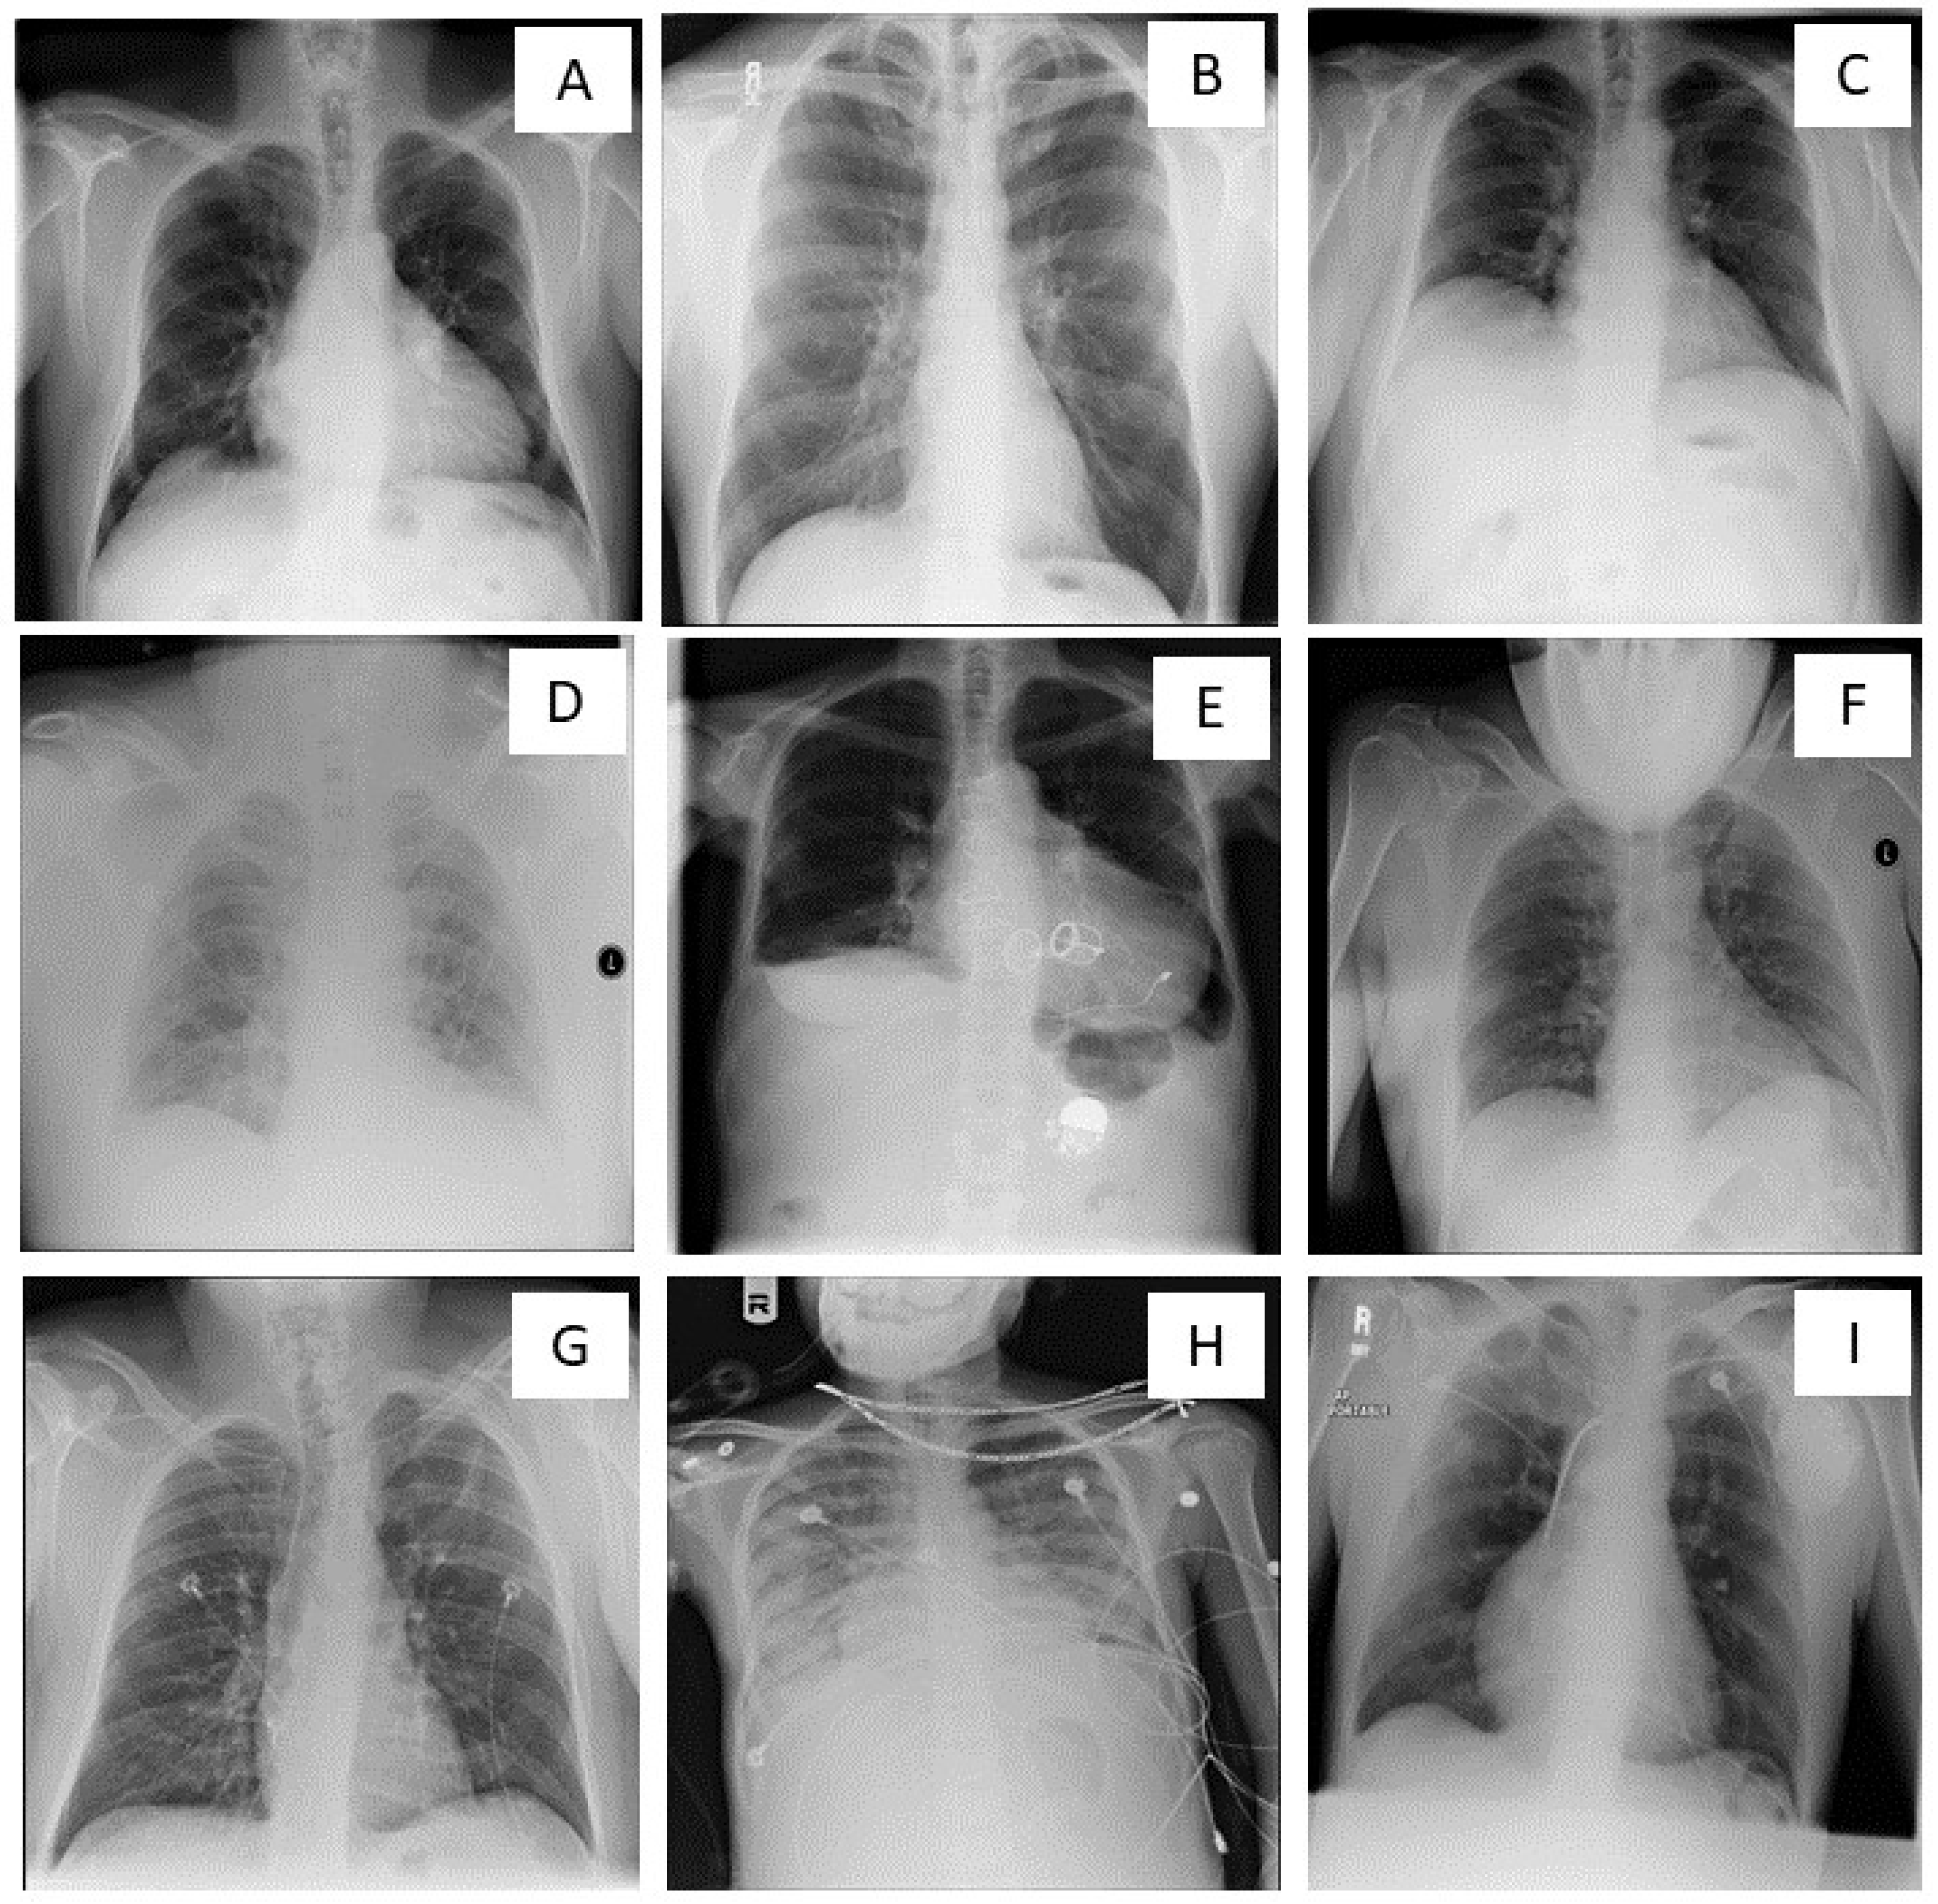

2. Optimal and Suboptimal CXRs: The Criteria

3. Suboptimal CXRs: The Problem

4. Suboptimal CXRs: Impact and Issues